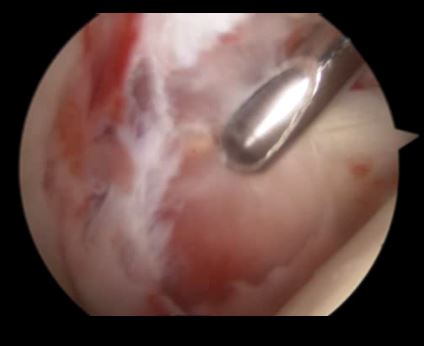

关节镜下可以彻底的清理关节内炎性滑膜组织及黏连带(盂肱关节及肩峰下关节)

黏连带

清理后 ,肌腱活动度明显改善